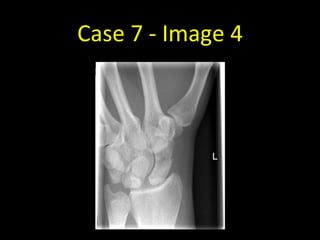

• 34 year old with pain in the anatomical snuffbox

Case 7 - Image 4

Case 7

• Scaphoid fractures can be notoriously

difficult to see. Four views are obtained

when a scaphoid fracture is suspected.

• A comminuted fracture of the waist of

the left scaphoid is visible on this

scaphoid series - this example is easier

to spot than most scaphoid fractures

• If a scaphoid fracture is still suspected

despite not being visible on radiographs,

the wrist should be immobilised and

repeat radiographs performed in 7-10

days at which time the fracture may be

more apparent.